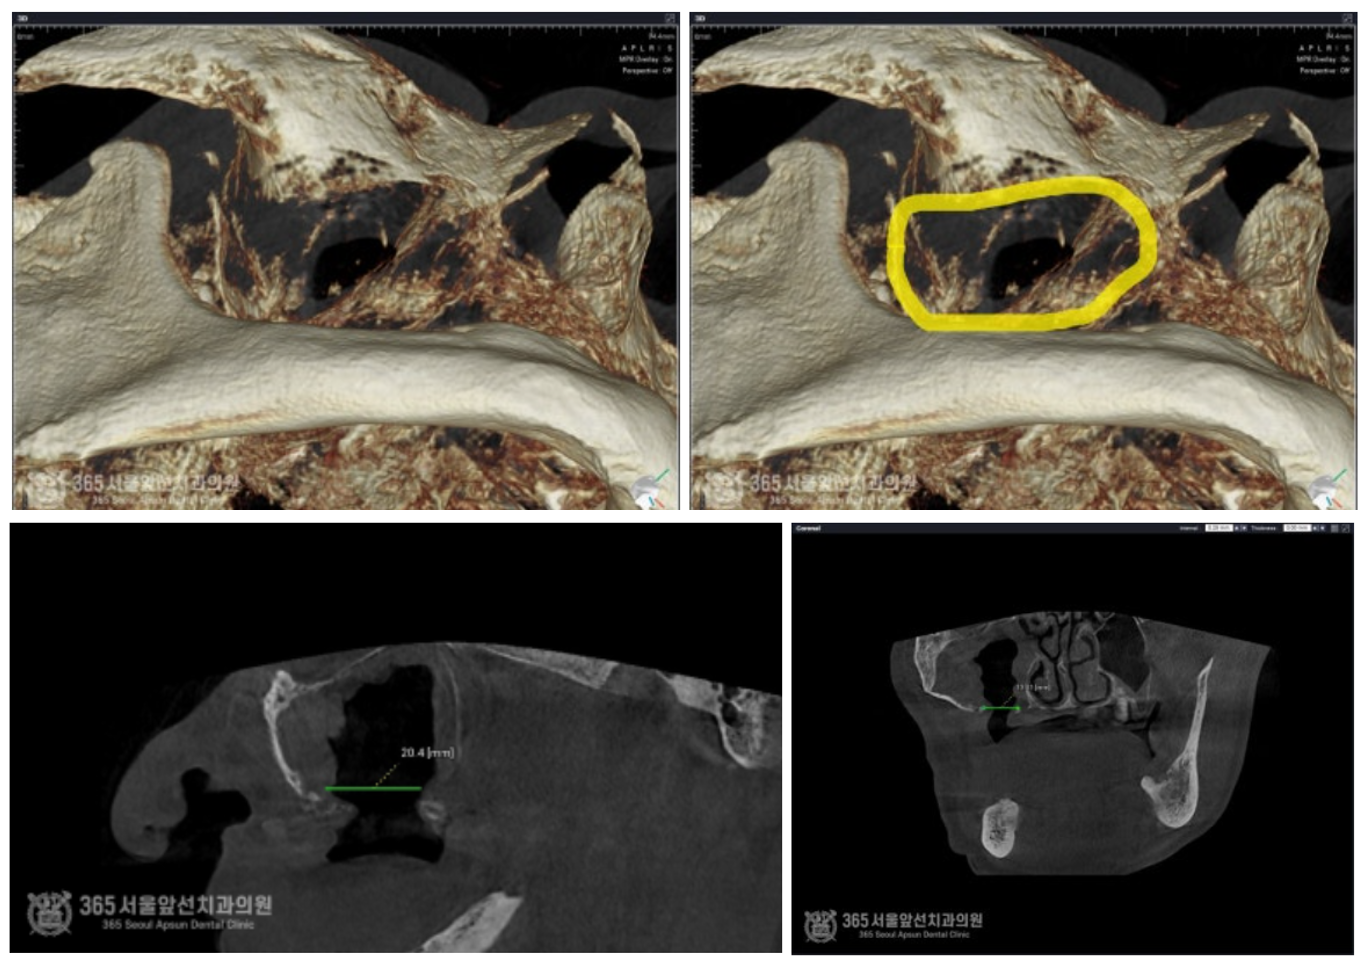

촬영일시 : 2024.07.05 CT 상에서 발생된 구강상악동누공의 크기입니다. 매우 커다란 누공이 존재함을 알 수 있습니다. 구강상악동누공 폐쇄술을 시행한 직후 구강내 사진입니다.